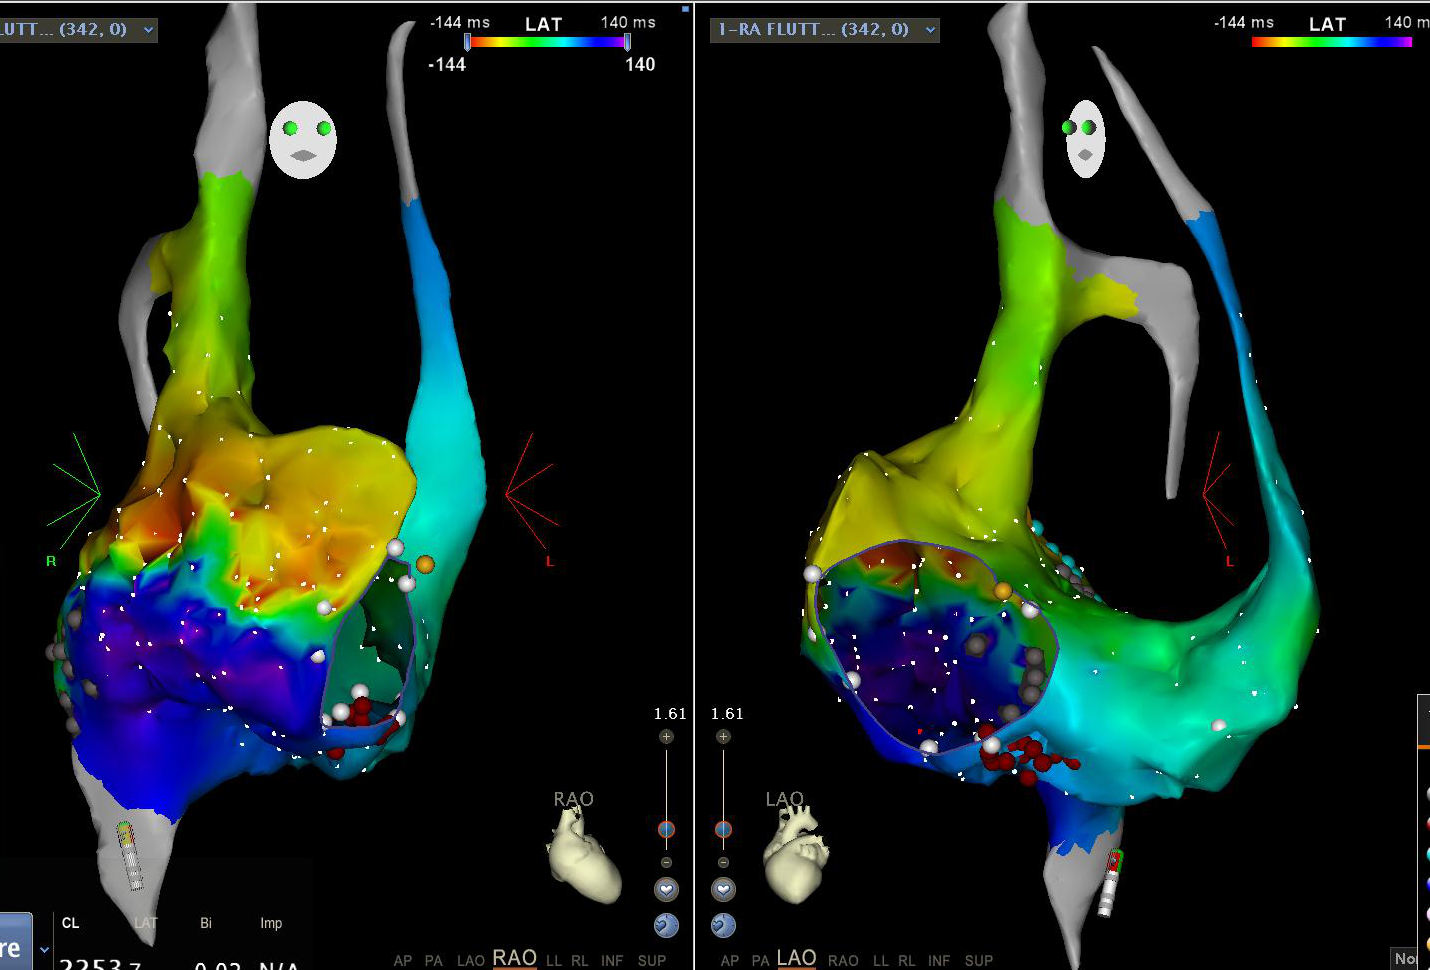

Activation mapping - Identify circuit

• Careful mapping with density

• Entrainment

Activation and entrainment

fig2.jpg

Activation mapping - Basics

• Selecting a good reference electrogram - Stable and reliable

• Setting WOI

• Consistent activation time marking

Atrial activation reference

rao_lao.PNG